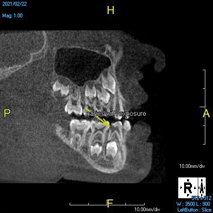

(4.) In a CBCT image axial view, the MB1 and MB2 canals are readily visible in tooth No. 14, and in the coronal view, these two separate canals can be seen to merge into a single apical opening.

Figure 4

(5.) In a CBCT image axial view, the MB1 and MB2 canals are readily visible in tooth No. 14, and in the coronal view, these two separate canals can be seen to merge into a single apical opening.

Figure 5

Being able to see the number and shape of the canals accurately prior to treatment is the desire of any clinician who performs endodontics. Research suggests that, due to improved diagnostic accuracy, the final treatment plan may change in up to 50% of endodontic cases if CBCT is used rather than traditional 2D imaging.14,15 The question of whether or not a patient has an MB2 canal can be answered prior to opening the access preparation (Figure 4 and Figure 5). Visualizing single canals that bifurcate in the apical or middle third of the root or those that merge to a single apical opening can help clinicians to understand their instrumentation needs in advance. In addition, the ability to measure the length and shape of a canal planned for instrumentation prior to utilizing an apex locator helps to confirm any measurements obtained by other means. It should also be noted that the ability to see a pathosis in 3 dimensions and to involve the patient in understanding his or her condition prior to any decision-making allows for definitive treatment planning. In fact, many patients have pathoses associated with teeth that are asymptomatic that remain unknown to them until they are visually presented with the evidence (Figure 6).